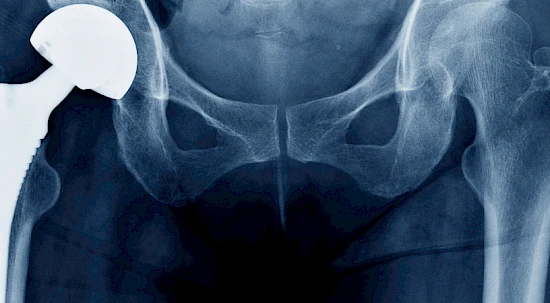

Ticino Welcome - Anche le protesi possono essere revisionate